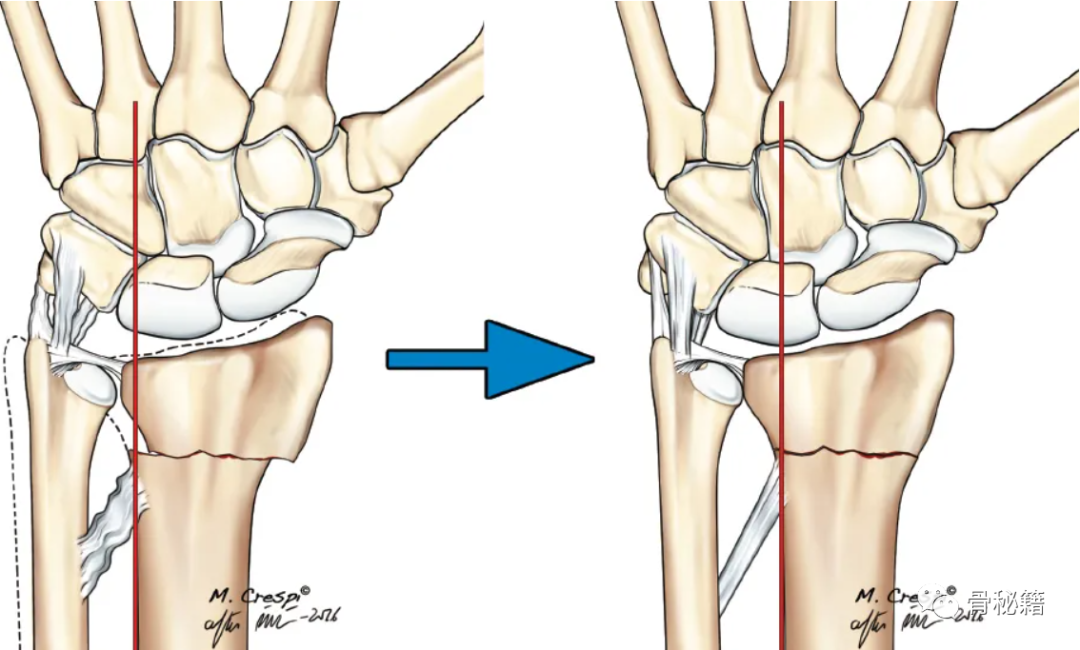

it was impossible to have shortening of the radius of more than 2 mm or 20 degrees of dorsiflexion without complete detachment of the TFCC from the fovea or the sigmoid notch.

曾经有学者研究,如果桡骨短缩2mm或成角20度,那么TFCC就可能有损伤,损伤的类型有多种多样。其中,红色损伤比绿、黄色损伤更容易造成尺骨远端不稳定,所以红色损伤时需要考虑手术治疗,尤其年轻患者。

需要注意的要点:如果桡骨复位不佳,可能导致下尺桡关节匹配问题及相关韧带松弛最终带来相关症状,注意看桡骨尺侧轴线的位置